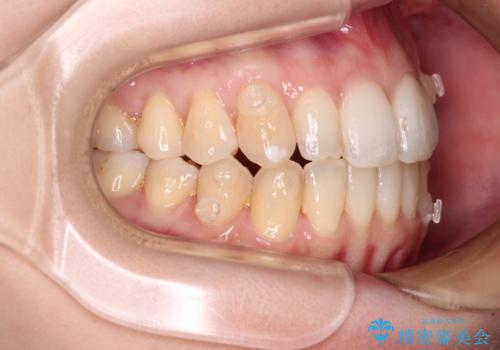

補助装置を併用したインビザラインでの八重歯の抜歯矯正

- 八重歯と奥歯の咬み合わせを気にして来院された患者様です。

インビザラインによる矯正治療を希望されたため、八重歯改善のための抜歯矯正部分は補助装置を併用し、その後はインビザラインにて行うこととしました。

骨格的に下顎が右側に変位していたため、上下正中を合わせることは困難であることは分かっていました。それでも、なるべく合わせるようにとしたため、治療期間は長期間となりました。